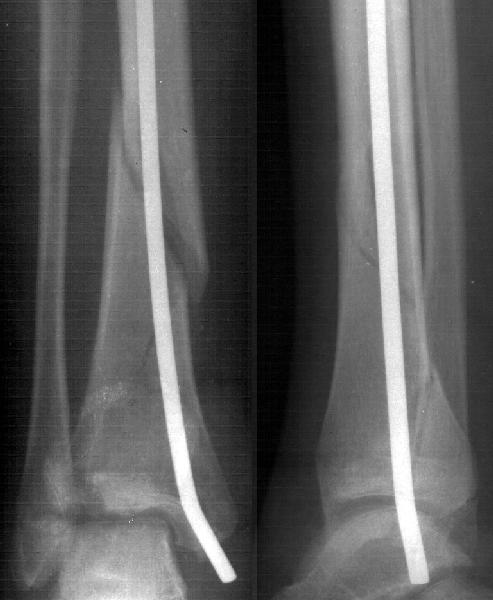

Девочка 14 лет полтора года назад оперирована в детской больнице по поводу спирального перелома костей голени (снимок 1)- выполнен закрытый остеосинтез стержнем Богданова, введенным ретроградно с медиальной стороны (снимок 2). Фиксатор после сращения удален

Мне в тоже время совершенно ясно видно по той же КТ, по 4 срезам, расположенным в центре и вверху пленки, что перелома внутренней лодыжки не было, в следующем собщении я приложу увеличенный фрагмент томограммы. А к этому письму прилагаю увеличеный фрагмент послеоперационной рентгенограммы, где выделил отколотый фрагмент

позади внутренней лодыжки. И он, как я вижу, находится между стержнем и тараном. А перелома внутренней лодыжки, и тем более смещения, IMHO

не определяется.